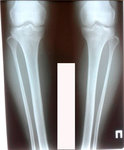

Исходник - 32 года.

Дата операции - 03.03.2020

Вложения

image-02-03-20-09-06-1.jpg